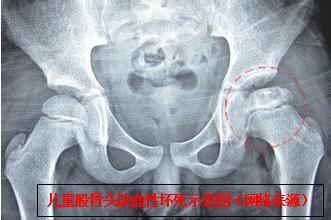

该团队相关负责人介绍,该患儿如不及时快速准确将脱位的髋关节整复,会引发并发症,进而导致股骨头缺血性坏死、髋关节生长紊乱、神经损伤、复发性脱位、创伤后骨关节炎、骨化性肌炎、股骨头创伤性分离。而其中最危急,要与时间赛跑的就是股骨头缺血性坏死,所以,必须在伤后24 小时内完成脱位髋关节的复位。

儿童创伤性髋关节脱位(traumatic dislocation of the hip in children,TDHC)发生率较低,临床甚为少见,年龄越小发生率越低。据相关文献报道,TDHC占所有髋关节脱位的5%~10 %,TDHC患儿一般在5岁以上,3岁幼儿病例报道基本罕见。如不能及时明确诊断及治疗,极易导致疗效欠佳及存留后遗症,严重影响患儿成长发育及日后功能活动。